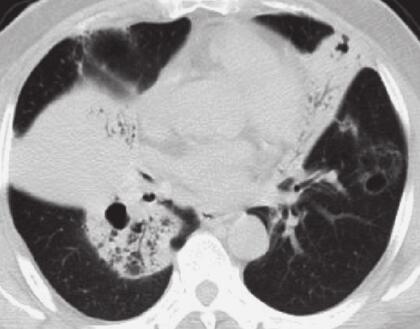

入院后给予左氧氟沙星注射液抗感染,盐酸氨溴索祛痰、多索茶碱解痉治疗,咳嗽、咳痰及呼吸困难症状改善不明显。2014年11月29日胸部CT示(图1):双肺可见大片状及片絮状高密度阴影,内可见通气征。2014年12月2日支气管镜检查提示:右肺主支气管及右肺中间段支气管充血明显,黏膜欠光滑,可见管腔轻度狭窄。活检病理提示:黏膜慢性炎症。患者感气喘,查体肺部可闻及散在哮鸣音。给予甲泼尼龙注射液40mg,1次/日,静点,3天后患者自觉气喘等症缓解,但仍有咳嗽及呼吸困难,夜间咳嗽明显2014年12月10日再次行支气管镜检查,给予TBLB,仍提示黏膜慢性炎症。请感染科会诊拟给予抗结核治疗。患者不耐受,拒绝行抗结核治疗。再次行支气管镜检查,TBLB,病理结果提示:左肺上叶舌段活检:结合HE形态及免疫表型符合B细胞非霍奇金淋巴瘤。右下活检:黏膜慢性炎,间质炭末沉积。

图1 2014年11月29日肺部CT

双肺实变病灶并伴有空气支气管征

2. 主要表现为反复咳嗽、咳痰、呼吸困难,查体双肺散在干啰音及湿啰音,胸部CT检查提示双肺大片状及片絮状阴影,可见支气管征,纵隔淋巴结肿大。反复行TBLB才明确诊断。

肺原发性淋巴瘤影像学表现多种多样。宋伟等将其归纳为:①结节肿块型:最常见,多为单发病灶,边界模糊,病灶内可见支气管充气征,部分病灶内可见空洞和液平;②肺炎或肺泡型:表现为沿肺段或肺叶分布的模糊斑片影,可见支气管充气征,偶见空洞;③间质型:最少见,表现为弥散的细或粗糙网状结构或网状小结节或毛玻璃样变;④粟粒型:表现为直径小于1cm的多发小结节,边界粗糙,无支气管充气征。本例属于肺炎型,见支气管充气征,未见明显肿块影,因而给诊断造成困难,一开始被误诊为肺炎,最终反复行TBLB才得以明确诊断。

下述表现有助于PPL诊断的可能:①年龄在60岁左右,无症状或咳嗽、咳少量痰,有胸闷、胸痛、呼吸困难等症状者;②肺部影像表现为结节、肿块或实变病灶并伴有空气支气管征,合并肺间质性改变,无肺门及纵隔淋巴结的肿大,无胸膜增厚及胸腔积液;③病灶变化趋势不大,并且长期存在。病理学是确诊的关键,而病理标本获取途径主要通过TBLB、PTNB、内科胸腔镜、VATS及开胸手术切除。对此我们的经验是,首先选用损伤性小、患者的依从性较好的方式,如TBLB、PTNB、内科胸腔镜下胸膜活检,并可多次活检以提高阳性率。但是若上述诊断方法仍不能明确诊断或诊断所需时间较长时仍应,再考虑采取VATS等外科介入方式进行活检、及时诊断。